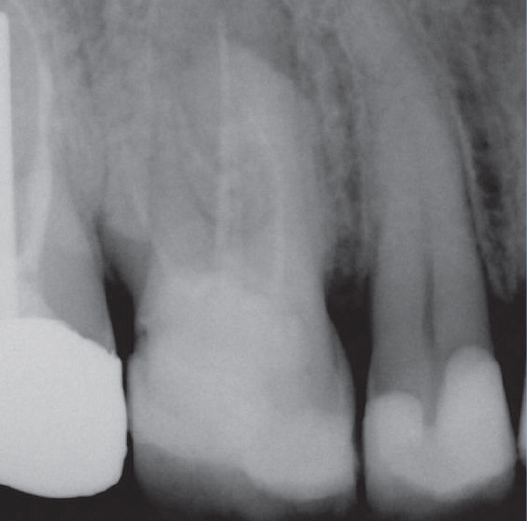

After

After Root Canal treatment